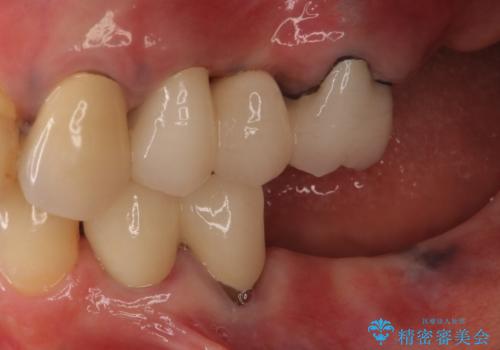

患者様はインプラント等の外科処置は希望されなかったため、セラミックと義歯で治療を行いました。

義歯を製作する際は、支えとなる歯の治療も同時に行うことで、義歯の製作が容易になります。

今回もそのように製作したところ、適合がよく安定のよい義歯になりました。患者様本人も使っていて全く痛くないとのことで、追加の調整もなく使用して頂いてます。患者様には、大変満足して頂きました。